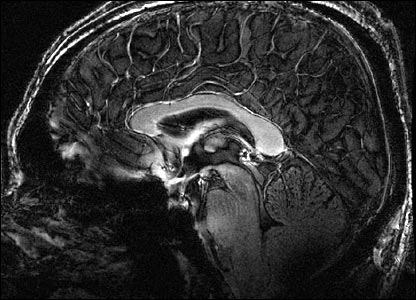

The scanner gives a much clearer image of the structures of the brain than less powerful machines.